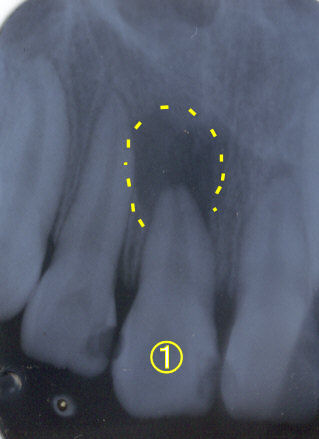

歯の根の治療

何度か腫れを繰り返した歯(7番)でした(写真1)。歯の根の治療は先の方まで薬が入っています。歯周ポケットは4mm程度で根の先まで交通していませんでした。根の先から亀裂が入っていると診断して矯正力をかけた後に一旦抜歯しました。やはり根の先に亀裂が入っていました。その部分のみを切断、逆根充して(写真2)再び抜歯窩にもどして固定しました。2ヶ月後に最終の冠を入れました(写真3)。動揺もなくしっかり噛めるようになったそうです。根の先の病変の影も薄くなっています(写真4)。 |